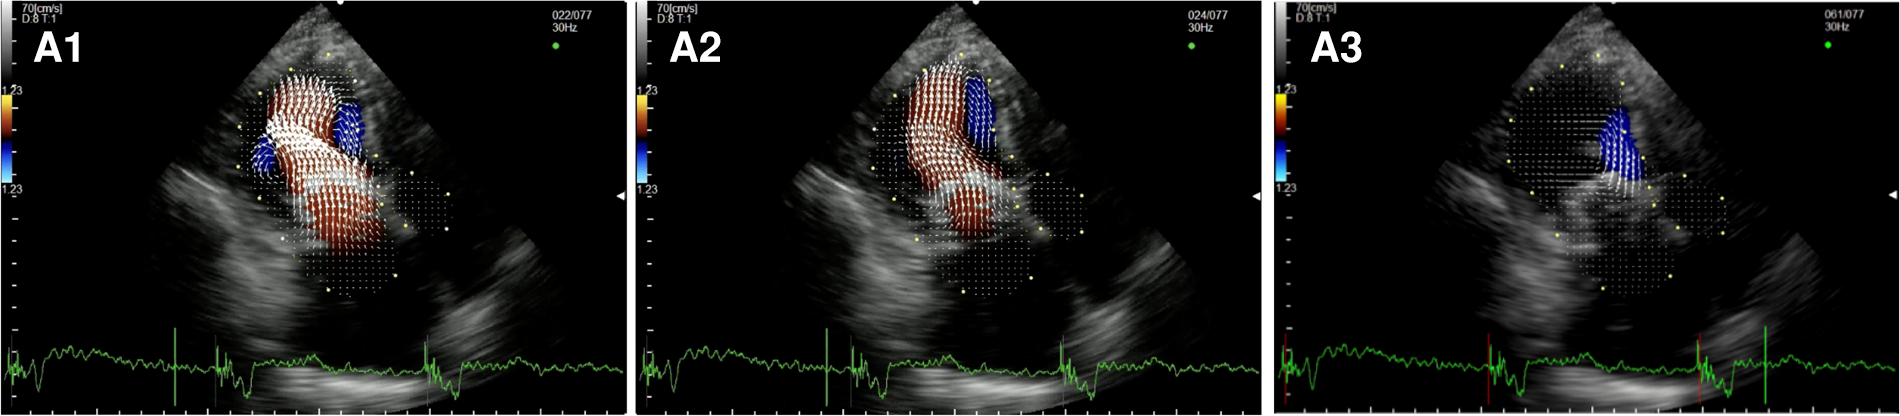

In the two subjects who underwent surgical implantation of a Sapien 3 THV (Figure 6, Supplementary Video S9), there was a pair of counterrotating vortices during diastole. Still, the main vortex had a counterclockwise rotation (opposite to the healthy control). In systole, hemodynamic forces were directed mainly along the left ventricle longitudinal axis, from the apex to the LVOT. Multiple secondary vortices occur throughout the cardiac cycle distal and proximal to the bioprosthesis.

Figure 6

Apical long-axis view. Intracardiac flow vectors in early and late diastole (A1,A2) and mid-systole (A3) after surgical implantation of a Sapien 3 valve in mitral annular calcification (MAC).

After Neochord Procedure (Figure 7, Supplementary Video S10), we observed a flow pattern that was similar to healthy subjects and patients who underwent surgical repair with a larger clockwise vortex below the anterior leaflet and the smaller counterclockwise one under the posterior leaflet during early diastole. Again we observed the displacement of the flow vectors towards the apical region during the later phases of the diastole and only mildly turbulent systolic flow in the LVOT.

Figure 7

Apical long-axis view. Intracardiac flow vectors in early and late diastole (A1,A2) and mid-systole (A3) after transapical off-pump mitral valve repair with NeoChord TM device.